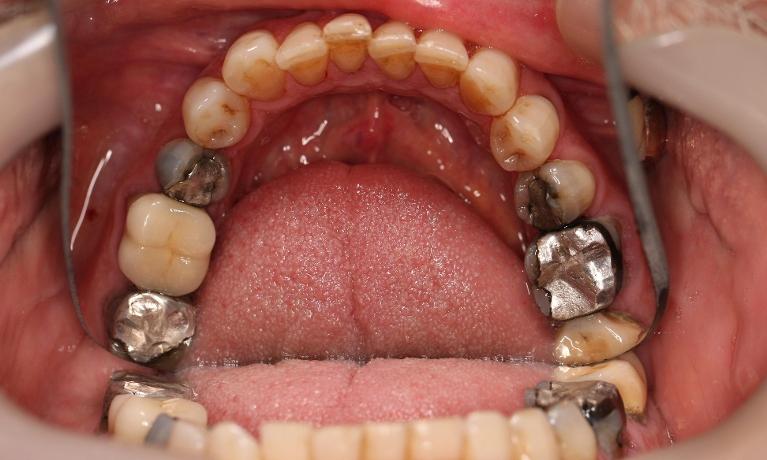

This man in his 50s was unhappy with the amalgam filling used to fix cavities. After discussing options, we agreed to fix his appearance by putting crowns on the teeth which create more of a natural look. This patient was very happy with the end result and is now in maintenance mode.